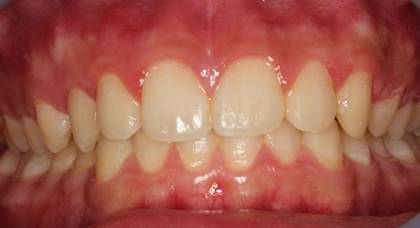

インビザGOによる矯正症例1 16歳男性

治療終了後10か月